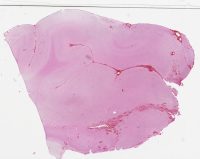

CANP2008-12.svs

44000 x 30645

@ 20X